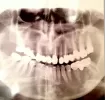

Снимок сделан перед началом замены коронок.